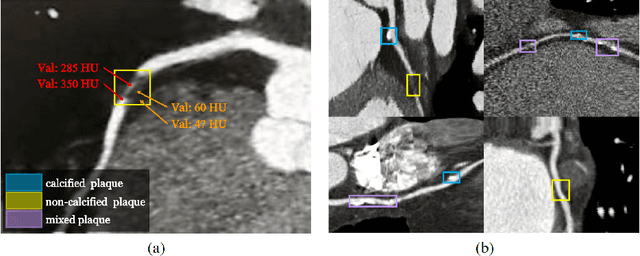

Abstract:Coronary artery disease (CAD) has posed a leading threat to the lives of cardiovascular disease patients worldwide for a long time. Therefore, automated diagnosis of CAD has indispensable significance in clinical medicine. However, the complexity of coronary artery plaques that cause CAD makes the automatic detection of coronary artery stenosis in Coronary CT angiography (CCTA) a difficult task. In this paper, we propose a Transformer network (TR-Net) for the automatic detection of significant stenosis (i.e. luminal narrowing > 50%) while practically completing the computer-assisted diagnosis of CAD. The proposed TR-Net introduces a novel Transformer, and tightly combines convolutional layers and Transformer encoders, allowing their advantages to be demonstrated in the task. By analyzing semantic information sequences, TR-Net can fully understand the relationship between image information in each position of a multiplanar reformatted (MPR) image, and accurately detect significant stenosis based on both local and global information. We evaluate our TR-Net on a dataset of 76 patients from different patients annotated by experienced radiologists. Experimental results illustrate that our TR-Net has achieved better results in ACC (0.92), Spec (0.96), PPV (0.84), F1 (0.79) and MCC (0.74) indicators compared with the state-of-the-art methods. The source code is publicly available from the link (https://github.com/XinghuaMa/TR-Net).